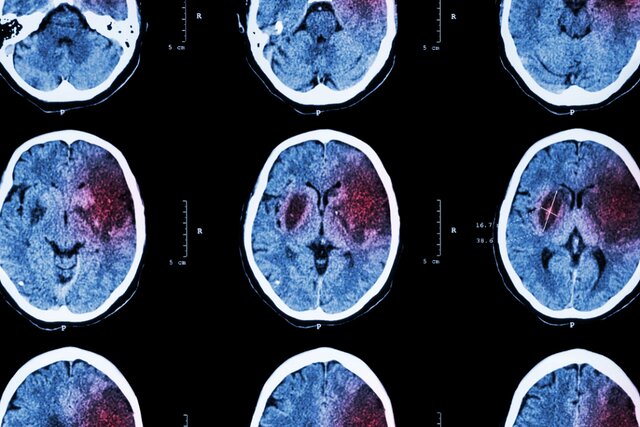

سکته مغزی ایسکمیک زمانی رخ میدهد که انسداد رگ خونی، جریان خون به مغز را متوقف میکند و به از بین رفتن نورونها منجر میشود. بازماندگان سکته مغزی ممکن است از اختلال در کنترل حرکت و گفتار و سایر ناتوانیها رنج ببرند و اغلب به توانبخشی بلندمدت نیاز داشته باشند.

این دارو با متوقف کردن بیان یک پروتئین گیرنده به نام "آلفا۲دلتا۲"(alpha2delta2) عمل میکند که پس از آسیبی مانند سکته مغزی، بیش از اندازه برانگیخته میشود و به جلوگیری از رشد آکسون میپردازد که میتواند آسیب را جبران کند. هنگامی که گاباپنتین بیان این پروتئین را متوقف کرد، نورونهایی در بخش آسیبدیده مغز دیده شدند که آکسونهای جدیدی از آنها جوانه زدند و سیگنالها را بازیابی کردند. آکسونهای جدید به حیوانات امکان دادند تا برخی از عملکردهای حرکتی خود را بازیابند.